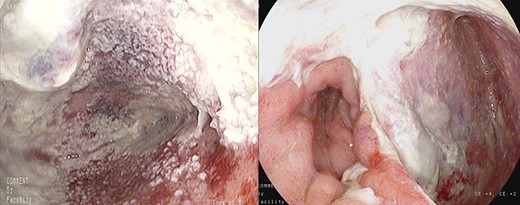

Healthy-appearing granulation tissue and progressive reduction of leak and cavity size.

The patient underwent 14 treatment sessions over 35 days. The leak and the cavity size progressively improved with the development of healthy-appearing granulation tissue s (Fig. 3). Inflammatory indexes and clinical conditions similarly improved. The endoscopic findings were confirmed by CT scans. Complications were not observed.